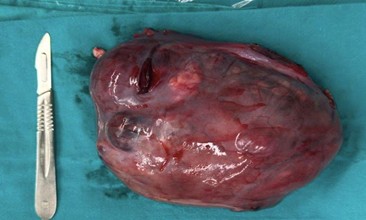

Luego de la evaluación integral e interdisciplinaria, se procede a realizar una laparoscopía exploradora. Los hallazgos intraoperatorios incluyen: tumor anexial derecho de 20 cm con evidencia de ruptura capsular previa (presencia de adherencias firmes de epiplón a la superficie tumoral), útero y anexo contralateral de aspecto normal y un implante peritoneal sospechoso en cara anterior periumbilical. Se toma biopsia de este último y de líquido peritoneal. Se realiza salpingo-ooforectomía derecha unilateral y omentectomía por características de los hallazgos intraquirúrgicos (ver imagen 3). La estadificación quirúrgica según criterios FIGO (2021) es Estadio IC2 (debido a la rotura intraabdominal previa a la cirugía).

Imagen 3. Fotografía de pieza quirúrgica. Voluminosa formación polilobulada con cápsula rota.